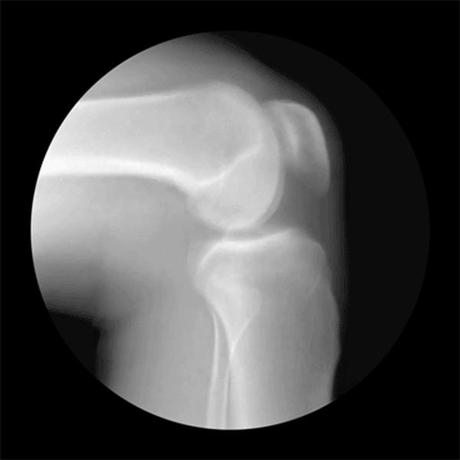

En este Gif vemos el movimiento de la articulación de la rodilla. La rodilla actúa como una bisagra, cuyas partes son el fémur, que está en el muslo, y la tíbia y el peroné, en la pierna. Esta articulación está protegida por la rótula.